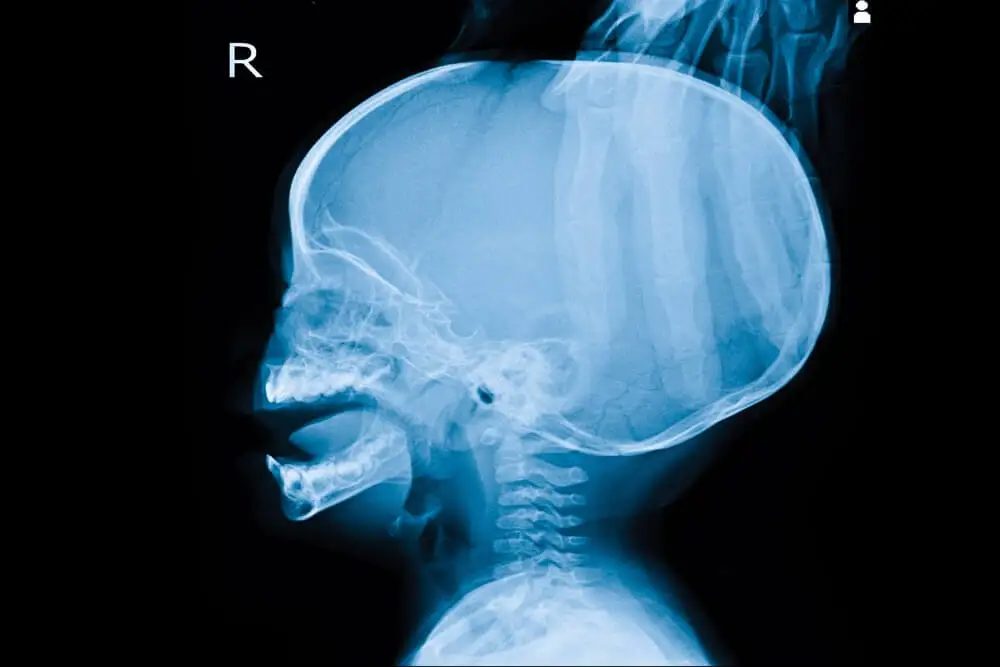

Hidrocefalia: síntomas y tratamiento

El organismo produce líquido cefalorraquídeo (LCR) continuamente. La hidrocefalia es un trastorno que se caracteriza por una acumulación anormal de líquido cefalorraquídeo (LCR) en el cerebro. Esa acumulación provoca un aumento excesivo de la presión en el cráneo.

En situaciones normales el LCR circula por el cerebro y la médula espinal a través de ventrículos, se almacena en depósitos conocidos como cisternas y pasa regularmente a la sangre. Si alguna circunstancia limita esa circulación, el líquido se acumula en ciertas regiones y ejerce una presión perjudicial sobre el tejido cerebral (hipertensión craneal). El exceso de presión intracraneal puede llegar a producir lesiones irreversibles.

- En bebés: separación exagerada entre los distintos huesos que forman el cráneo, y por lo tanto un agrandamiento anormal de la cabeza.

- En adultos: fuertes dolores de cabeza debido a que los huesos que forman el cráneo ya están formados y fusionados y no se pueden desplazar para dejar espacio al líquido.